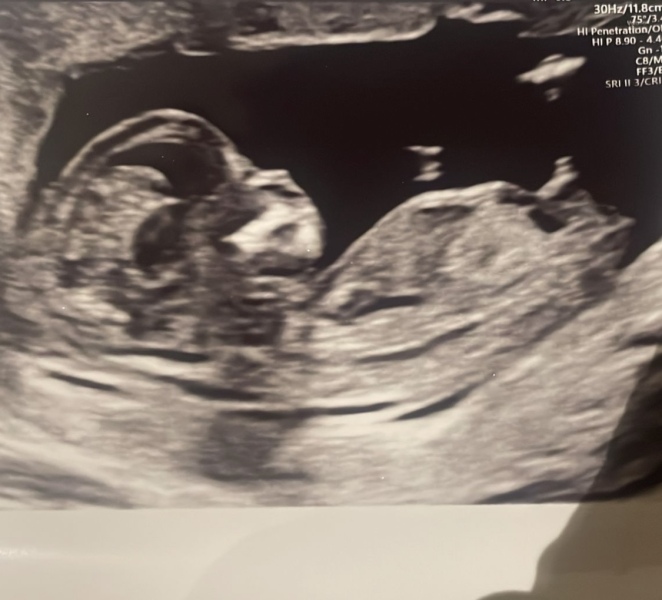

Hello! Would really love your views… can’t work out whether the bit that might be a very obvious boy nub is actually a leg/cord?! Or just actually a boy nub…